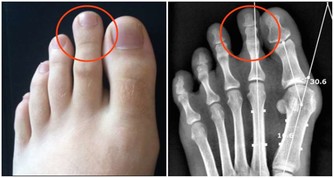

外八字走路,久而久之膝蓋也會外移,雙腿變成X型。這些人上了歲數就會出現關節痛疼,加速關節老化。林華表示,有很少的一部分人,鞋跟內側磨得厲害,通常這些人走路姿勢呈內八字形,需要到骨科矯正。琥珀帶3個月,身上的疾病減輕了,因為內八字背後還藏著一些疾病。臨床上,一些佝僂病、脛骨發育有問題的患者走路常常是內八字,除了「O形腿」,還可表現為「X形腿」。

鞋底內側磨損較多

可能是兩腿的膝關節向外分離,導致小腿脛骨向內翻轉一定角度。嚴重的話會形成O形腿或「內八字」。如果邁著外八字腳步,說明腳趾向外的角度過大,時間久了,會讓膝蓋外移,雙腿變形。隨著年齡增長,可導致膝關節疼痛以及加速關節退化,甚至引起腰椎不適。

4、鞋底內側的磨損較多

鞋底內側的磨損較多,俗稱內八字,腳板過度內翻或是先天性的扁平足,膝關節向內側壓縮,易導致關節扭傷、損傷。

B.鞋跟內側都出現磨損

這種情況,是因為兩腿的膝關節向外分離、小腿脛骨向內翻轉了一定角度造成的。如果磨損十分嚴重,就意味著你的膝蓋已經外移,雙腿已經變形,變成「O形腿」或「內八字」。

隨著年齡增長,這種情況容易導致膝關節疼痛以及加速關節退化,甚至引起腰椎不適。